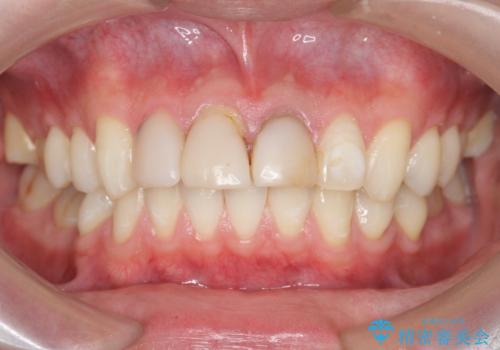

前歯の変色 審美性の改善

- 前歯の変色や形態を含む、見た目を改善したいと希望され来院されました。

視診・X線検査・歯周組織検査より下記のような問題が列挙され、長期的な予後を見込むために一つづつ問題の解決を計ります。

・不十分な根管治療 →マイクロスコープを用いる精密根管医療

・歯の変色 →ジルコニアクラウンの製作

・歯肉縁下カリエス →部分矯正による歯の挺出・歯周外科